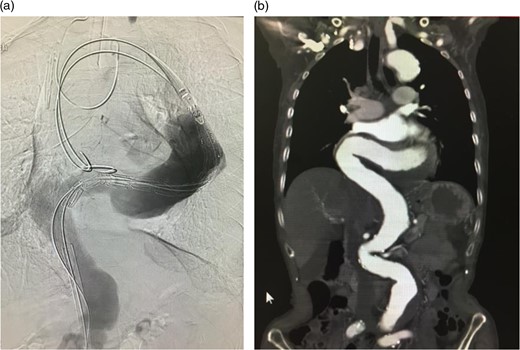

The stent graft (Relay Plus® 38 × 34 × 200 mm, Bolton medical, Barcelona) was introduced through the right common femoral artery. When it reached the distal site of the thoracoabdominal aorta where the angulation was the most severe, the outer hard sheath was left there while the inner flexible sheath was advanced. The flexible sheath was successfully introduced to the proximal site of the thoracoabdominal aorta beyond the angulation (Fig. 3). The stent graft was placed and we confirmed that no endoleak existed (Fig. 4).

Intraoperative arteriogram. (a) The hard sheath was left at the distal site of the angulated part and the flexible sheath was advanced. The angulation was sufficiently reduced by additionally introducing delivery devices for the stent graft (sheath and guide wire). Thus, the stent graft was introduced to the proximal side of the angulated part beyond the aneurysm. Compared to the preoperative contrast CT coronal section image (b) a reduction in the angulation of the proximal aneurysm was observed.